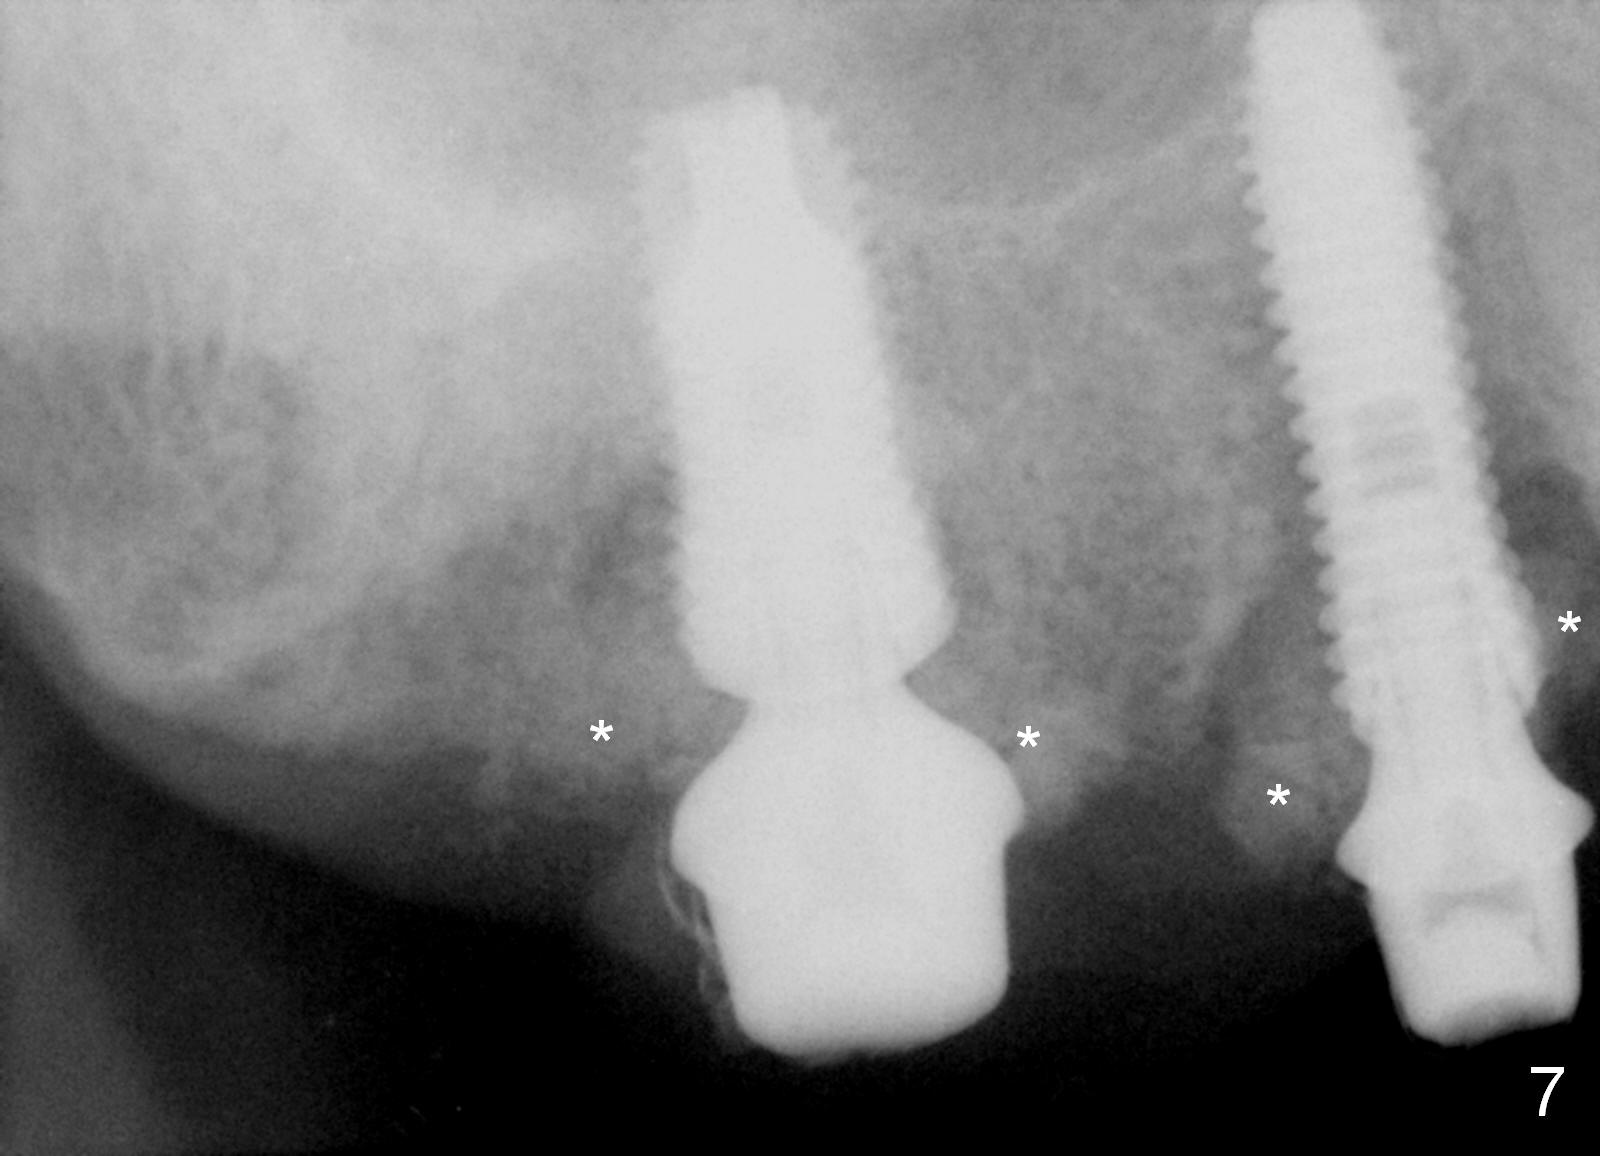

Preop photos show generalized gingival hyperplasia (hypertension med (Amlodipine, Calcium Channel Blocker), Fig.1 *), palatal (Fig.2<) and buccal (Fig.3 B) abscesses originated from the tooth #5. There is a smaller abscess buccal to the tooth #3 (not shown). After extraction, the buccal and palatal plates of the teeth #3 and 5 are found basically non-existent. When taps are placed, large socket defects are evident (Fig.4 *). In addition to sinus lift at #3 (Fig.5 black *), mineralized cancellous and cortical allograft (.5-1 and 1-2 mm) is placed around the implants with healing screws in place (white *). After the healing screws are removed and cemented abutments are placed, more allograft is packed (Fig.6-8 *). Closing the "dead" space in step may prevent immediately postop infection and peri-implantitis.

There is no infection around the implants 1 months postop (Fig.9,10). In fact infection mesial to #6 is more severe than preop (Fig.9 arrowhead, Fig.11). When the provisionals are removed for trimming, there is yellowish bone graft around the abutments, which is apparently not incorporated by the body (Fig.9,10 *). It is easily removed by spraying water. The margin of the abutment at #5 is subgingival; an abutment with a longer cuff should be changed next visit.